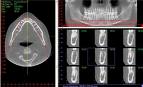

54m² e terá como destaque o moderno tomógrafo computadorizado

3D de tecnologia CONE BEAN, o i-Cat, fabricado pela

empresa americana Imaging Sciences. Trata-se de um tomógrafo

odontológico diferenciado pois expõem o paciente a uma

radiação até vinte vezes menor em comparação aos tomógrafos

médicos, além de imagens de alta definição, para diagnósticos

tridimensionais mais precisos, facilitando o planejamento